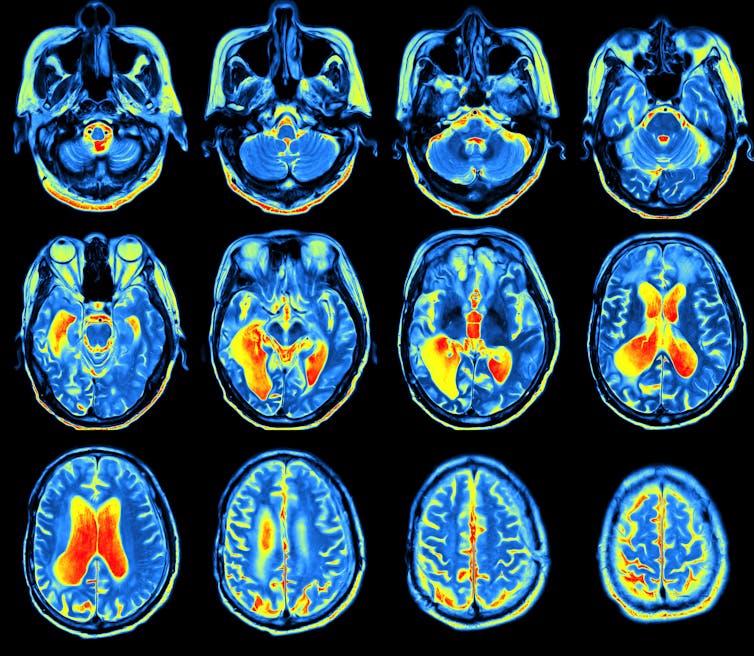

Brain scans show that this “reading network” is apparent in pretty much the same place in the brain in everybody. It forms when we learn to read and strengthens connections between our brain’s language and speech regions, as well as a region that has become known as the “visual word form area”.